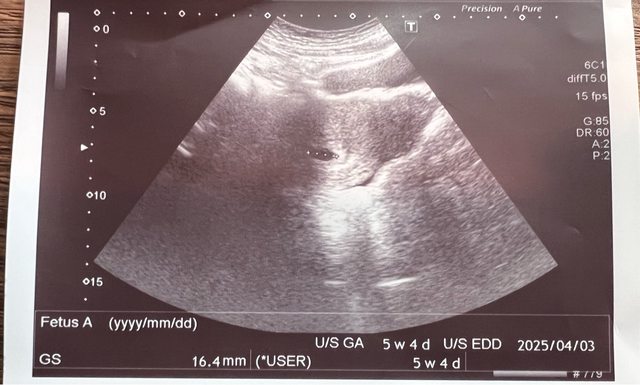

最後一次月經來是6/22 8/5 產檢看醫生 顯示胚囊5w+4d https://i.imgur.com/Ab9QSb4.jpeg

第一次給醫生看的時候 他說有可能有宮外孕的機率 如果這幾天有肚子痛什麼的再回診 8/19 二週後回診 今天有照超音波+內診 因為這超音波時,醫生說我子宮有點後頃 沒有照到東西 就換宮內診 照出來胚囊7w+2d,胚囊變大大概3公分 醫生宮內診有照到卵黃囊,但是沒有心跳 醫生看完後覺得我蠻大的機率是胚胎有問題 第一胎因為在國外生的 那時候也都沒什麼問題 第一次遇到醫生這樣說 整個驚嚇到 要我一週後再回診 說這週有可能會自然流掉 大概跟我說可能遇到的情況 注意有沒有大出血 如果沒有 可能就要安排手術了 今天照的照片忘記拿 有點被嚇到恍神 請問大概需要等幾週在決定要不要手術呢? 我打算週五再掛別的醫院的醫生確認一下 附上第一胎6w的照片 https://i.imgur.com/qlJ5n0e.jpeg